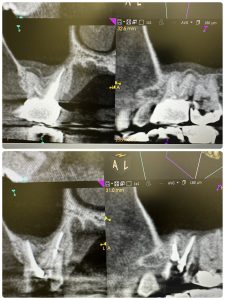

次は昨年セットした方

病巣も治癒、マージンラインの整合制がテーマ

歯冠延長術やら駆使